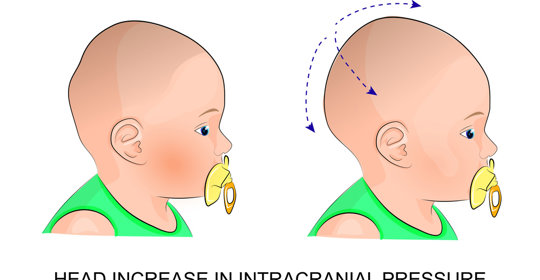

嬰兒:搖晃傷害自愈、喚醒策略、剃頭風險